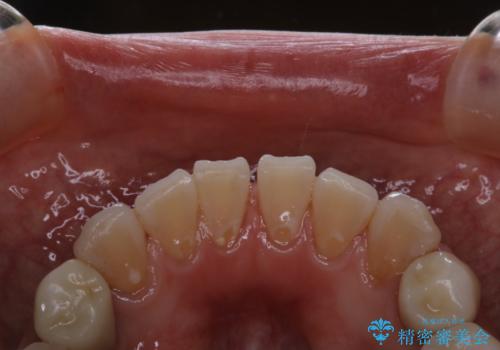

PMTCとはProfessinnal Mechanical Tooth Cleaning・専門器具による歯の機械的な清掃です。

外からは見えない歯周ポケットに汚れが溜まると、歯周病菌が増殖します。歯ブラシが届かない汚れには、歯科でのクリーニングが必要です。

PMTCで、バイオフィルム(細菌の塊)を破壊し、歯の表面をツルツルにすることでお口の中の細菌数を減らし歯周病のリスクが定着するのを防ぎます。更に、歯に新しい汚れがつきにくい状態になります。

バイオフィルムが除去されると、ご自身本来の歯の表面になります。PMTCをすることで口臭予防にもなり、定期的に行うことが大切です。